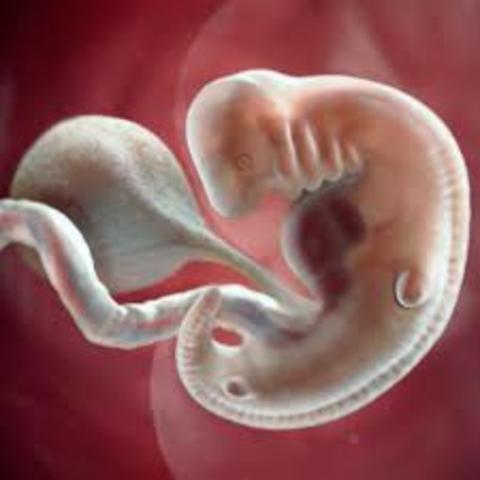

• Semana 6

Semana 6

En esta semana es cuando el corazón comienza con

latidos regulares que por lo regular no se detectan

aun en la ecografía, también comienza a tener

ligeros movimientos que aún no se perciben pues su

tamaño es de aproximadamente 1 centímetro de

largo.Progresa el desarrollo de la traquea, la laringe

y bronquios. Lacavidad oral y nasal comienzan a

separarse, se forma el paladar. Se desarrollan más la

piernas y los brazos que parecen aletas.

• Semana 7

Semana 7

Se pueden observar las yemas o también llamados brotes de brazos, las extremidades inferiores en forma de pala y la placa de la mano, también pudiendo ver algunos nervios del cráneo. Esta etapa es denominada organogénesis siendo un periodo importante en la formación del bebé pues es aquí donde se pueden crear mal formaciones.